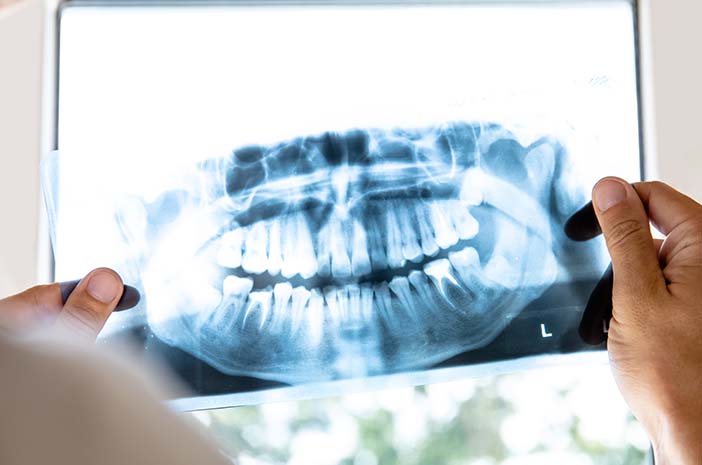

Mengapa Sebelum Pasang Behel Harus Foto Panoramik dan Cephalometri?

Anggelia Gita Tiyananda A.Md.Kes.(Rad)

Halo, Sobat Jo! 👋 Sebelum memasang behel, dokter gigi biasanya akan menyarankan untuk melakuka...

Rontgen Gigi Panoramic

Biaya Pemeriksaan Foto Rontgen Panoramic

Rp 125.000